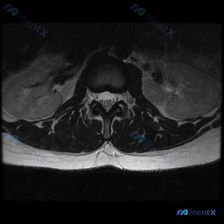

这是一张腰椎中下段的轴位T2加权MRI,影像观察结果如下:

- 椎间盘情况:椎间盘后缘平整,没有明显局部突出/膨出,髓核中央T2高信号,提示水分含量尚可、退变较轻,也没有看到明确的纤维环撕裂高信号(HIZ)

- 椎管与神经:硬膜囊形态规则没有受压,双侧侧隐窝空间宽敞,神经根没有受压变形,椎管没有狭窄,硬膜外间隙清晰

- 骨性与韧带结构:椎体后缘骨皮质连续光滑,没有骨赘增生;关节突关节间隙清晰,没有肥大增生;黄韧带厚度正常,没有肥厚钙化

影像结论:这个层面未见明确的腰椎间盘突出、椎管狭窄或严重退行性改变。